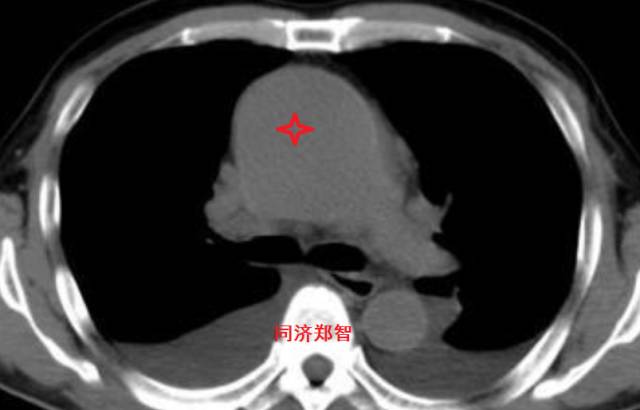

■ 病例二

胸部平扫CT提示升主动脉增宽(红色星形标记),CTA证实A型主动脉夹层伴升主动脉夹层动脉瘤形成。